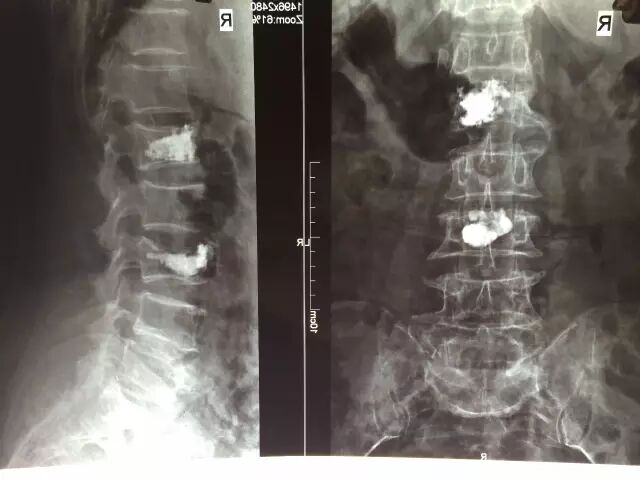

据珠海广安手足外科医院骨科主任谢业东介绍,经皮椎体成形术与后凸成形术是指在影像引导和监测下进行的微创治疗,经皮穿刺到椎体病灶内并注入骨水泥聚甲基丙烯酸甲酯(PMMA)等灌注剂,PMMA注射后1小时可达到最大强度的90%,通过一系列机械性、血管性、化学性、热效应等因素,起到止痛、增加椎体强度、预防塌陷、抑制肿瘤生长等作用。该项手术适应症宽,例如:胸腰椎骨折、帕金森氏病、心脑血管病等老年患病人群均可凭此微创手术得到良好治疗;

在广安医院通过经皮椎体成形术治疗的数位患者中,年龄均在50岁以上,大多数患者都具有骨质疏松引起的腰椎骨折或疼痛疾病等特征,在该项微创手术治疗后,均得到明显的治疗效果,疼痛缓解率超过90%,有的病人刚来就诊时不能自行翻身,术后6小时便可自行翻身坐立,疼痛减轻,效果显著。